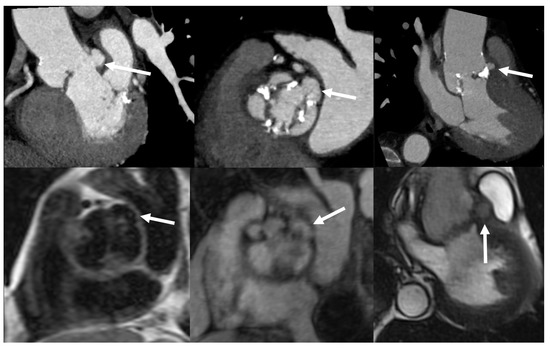

4.3. Role of CCTA in Diagnosing IE and Local Complications

6.3. Role of CCTA in Diagnosing PVE and Local Complication

- Feuchtner, G.M.; Stolzmann, P.; Dichtl, W.; Schertler, T.; Bonatti, J.; Scheffel, H.; Mueller, S.; Plass, A.; Mueller, L.; Bartel, T.; et al. Multislice Computed Tomography in Infective Endocarditis. J. Am. Coll. Cardiol. 2009, 53, 436–444. [Google Scholar] [CrossRef] [PubMed]

- Entrikin, D.W.; Gupta, P.; Kon, N.D.; Carr, J.J. Imaging of infective endocarditis with cardiac CT angiography. J. Cardiovasc. Comput. Tomogr. 2012, 6, 399–405. [Google Scholar] [CrossRef]

| Left-sided IE | Good visualization of mitral and aortic valve. Valvular dysfuction assessment. Identification of complication (i.e., valvular regurgitation). | Difficult differential diagnosis in presence of marantic vegetations or high calcification. | Detection of vegetations and valve perforation. Assessment of perivalvular extent of disease (abscesses, pseudoaneursysm, fistula). | Inferior to TTE/TOE in detecting small vegetations (<2 mm). | Prognostic assessment: simultaneous detection of embolism, metastatic lesions and portal of entry. | Limited sensitivity for small vegetations. | Evaluation of distant emboli and portal of entry. | Limited role because of low sensitivity for small vegetations. | Capability to assess vegetations (inferior to TTE/TOE). Capability to assess local complications. Independent by acoustic window. May detect concomitant myocardial inflammation. | Not included in current guidelines for IE diagnosis. |

| PVE | Routinely used for follow up; it allows sequential assessment of prosthesis function. TOE is often required to correctly assess the prosthesis. | Limited by prosthetic material artifacts (i.e., acoustic shadow). Early complication (i.e., abscess) can be difficult to identify. | Identification of complications (paravalvular leakage, abscesses, pseudoaneurysm, dehiscence, and extension to adjacent structures). Capability to visualize large vegetations (>10 mm). | Low image quality for beam hardening artifacts. Limited in assessing small vegetations (<4 mm). | High diagnostic accuracy. Good assessment of perivalvular/periprosthetic complications. Reduction of rate of misdiagnosed PVE. Role in prediction of MACEs. Prognostic significance. | Host reaction may reduce specificity (risk of false-positive studies until 3 months after surgery). | High specificity for infection. Reduction of rate of misdiagnosed PVE. Differential diagnosis between septic and sterile vegetations. | Limited sensitivity for small lesions. | Image quality severely hampered by susceptibility artifacts (especially from mechanical prostheses). | |